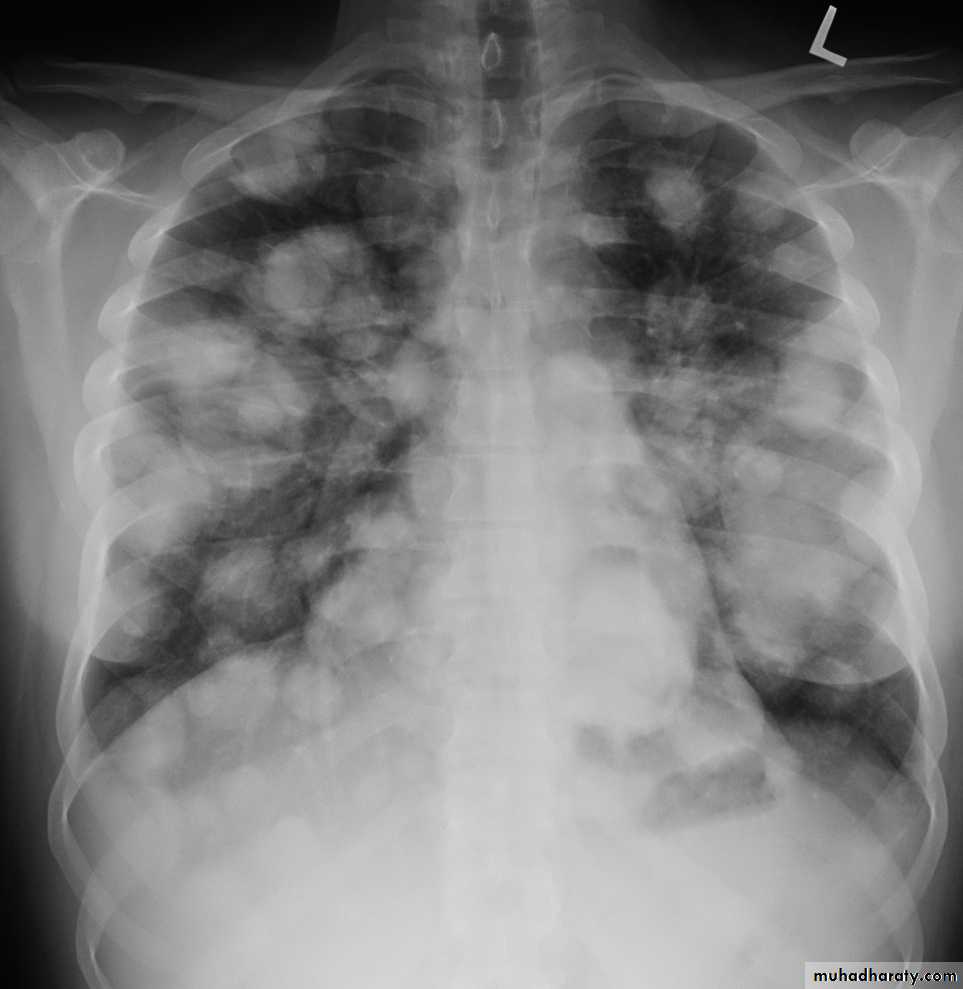

Secondary metastasis

74. secondary metastasis to the lung ( canon ball appearance )